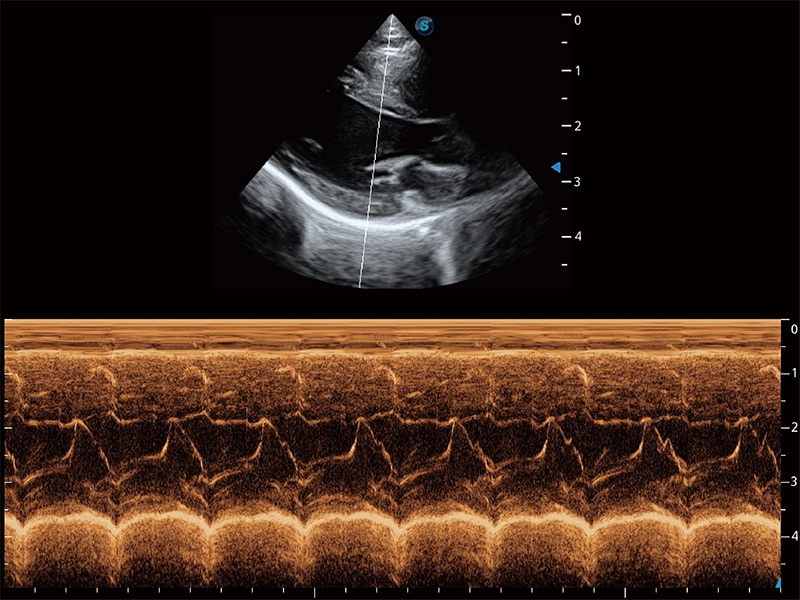

通过360度任意调节3条M型取样线,在同一心动周期上观察心脏不同位置的运动曲线,得到准确的心功能测量数据,有效评估心肌运动及左心室功能。

实时用颜色表示心肌组织运动,观察和定量组织的运动情況,对快速检测与评估心肌的灌注和活性、电传导及心肌收缩和舒张功能等均能提供重要的诊断信息。

能够增加心肌组织与血流之间的区别。对于心脏扫查困难的动物,可提供更好的心内膜边界的显示。

能够基于左心室壁追踪和辛普森法,自动计算射血分数,支持多个可移动点描迹,与手动测量相比,极大节省了动物医生的时间和精力。